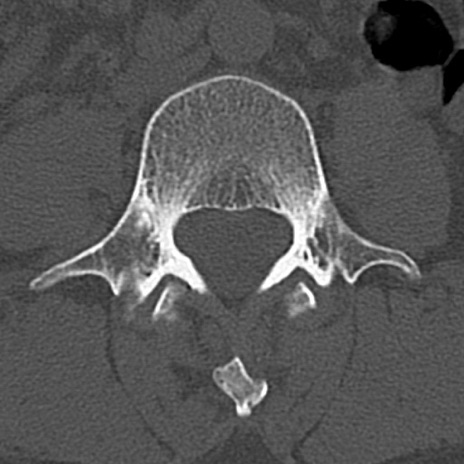

【整形】TIPS症例4 腰椎CT(横断像)

腰椎CT

横断像と矢状断像